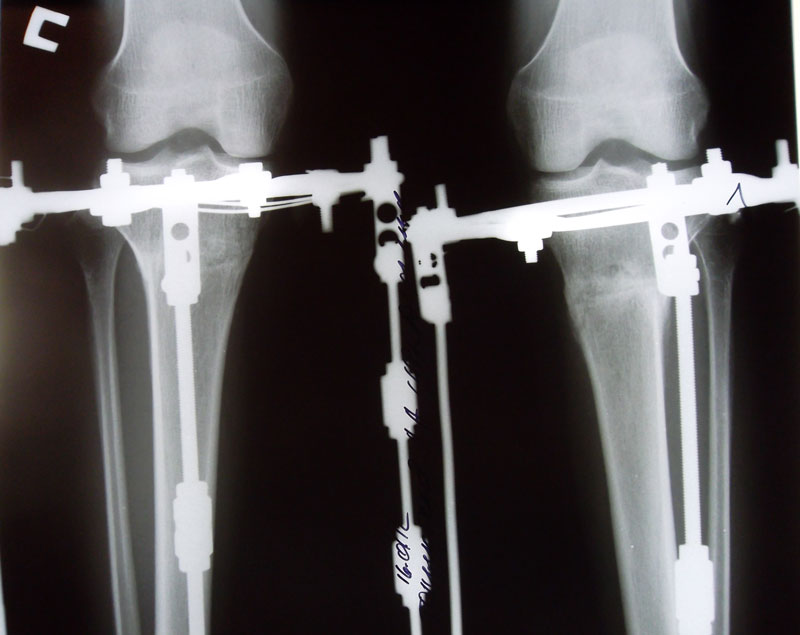

Рентгеновские снимки в день снятия аппаратов. 80 дней с момента операции.

Вложения

SAM_1450.JPG

SAM_1452.JPG